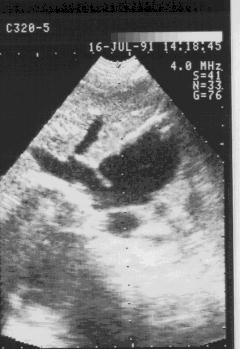

Аневризматическое выпячивание межпредсердной перегородки

в сторону правого предсердия в области овального окна.

Рис.160

Аневризматическое

выпячивание

межпредсердной

перегородки в сторону

правого предсердия в

области овального

окна.